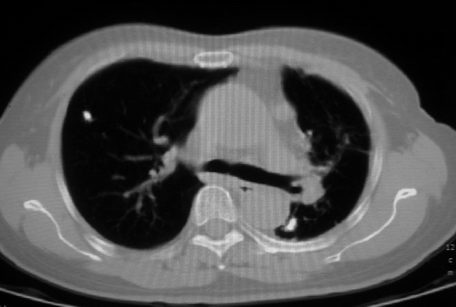

以下是引用李衡钧在2008-7-24 14:24:00的发言:[br]左侧胸廓变小,左肺上叶见大面积致密阴影,其内有空洞及不规则钙化。上纵隔略向左移位,上肺胸膜增厚。左肺门及纵隔淋巴结增大。右肺见散在的致密结节影。[br]印象:继发性肺结核。